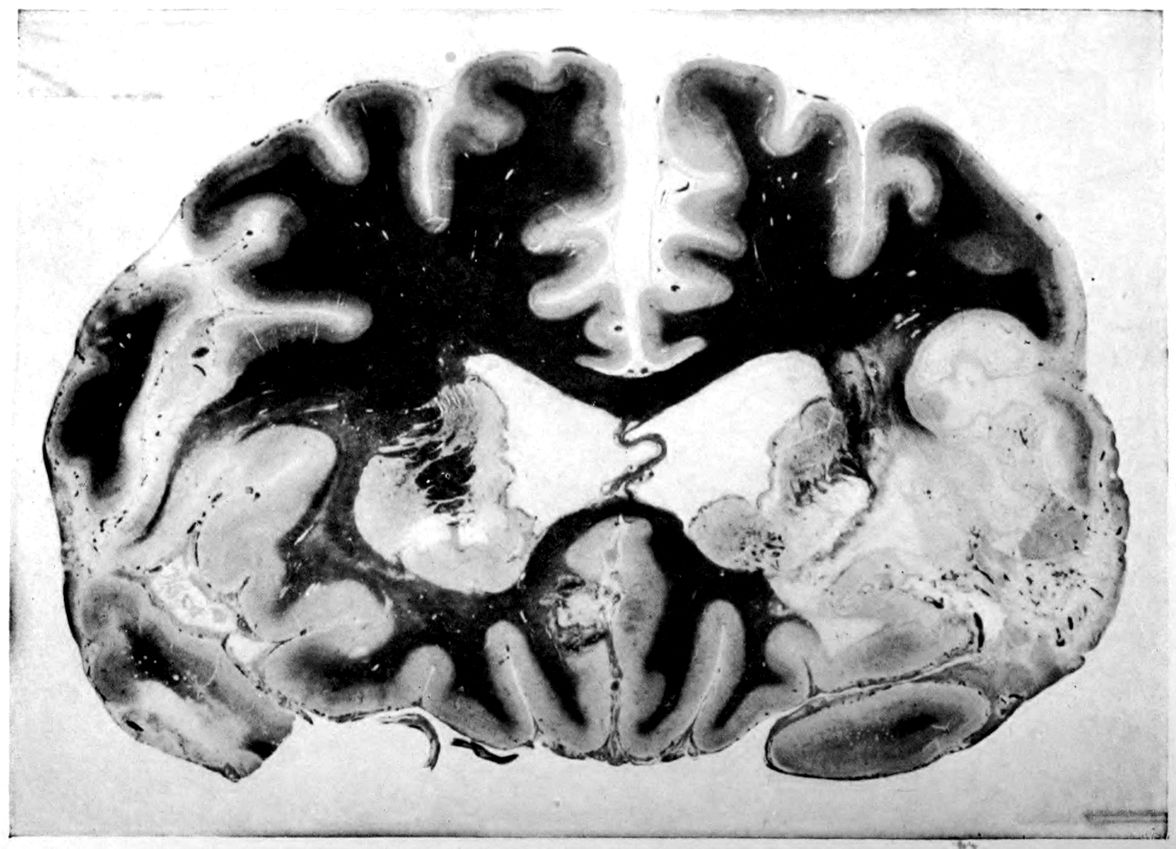

Vascular neurosyphilis—effects of syphilitic thrombosis of Sylvian artery 10 years before death. (Case 4.)

Case 4. (See previous figure for brain lesion.) Three levels of the spinal cord showing unilateral pyramidal tract sclerosis, 10 years after cerebral thrombosis.